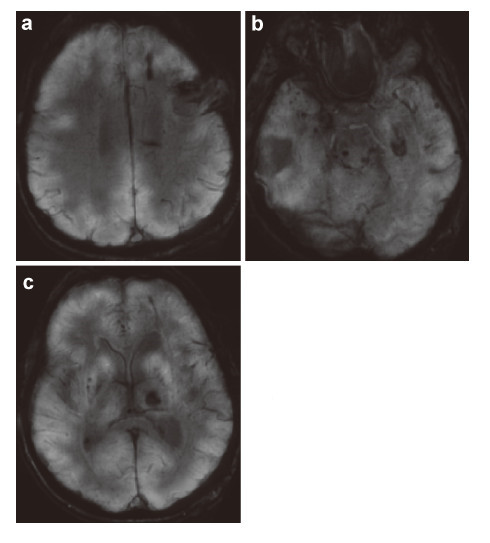

The obtained multi‐level data about the condition of the patient’s brain must be provided at contemporary carriers (CD,DVDs,flash drives,etc.) for the bioinformation analysis and they must be recorded in DICOM standard. The requirements for the research at this stage are the following: (1) No less than 1.5 Tesla MRI. (2) MRI tractography of conduction pathways in the site of injury of the brain/spinal cord. (3) MRI angiography of the brain vessels. (4) PET of the brain or a whole body,for spinal cords the standard radioisotopes of glucose PET must be done. (5) No less than 32 slice spiral CT of the brain or the spinal cord and spine. (6) Cerebral EEG mapping must be on the EEG equipment with the software for 3D local modeling of the bioelectrical activity of the brain/spinal cord. (7) MEG of the brain with 3D modeling.

The time period between different imaging tests should be not more than a week. All imaging tests that were done at the preparatory stage for the examination can be used at the next stage to monitor the effectiveness of the therapy. The imaging data can be fused into 3D maps of the brain with the help of the Multimodal fusion 3D software of the Cyberknife robotic radiosurgery system or similar systems for stereotaxic radiotherapy of other manufacturers. With this approach a three‐dimensional multi‐level mapped model of the information structure of the damaged NT of the brain/spinal cord of the nerve or mental disease case can be represented as the set of the tables of local data,that correlate them with anatomical formations in the brain so that the personalized functional 3D map of pathological changes and damages the NT of the specific case. Such a 3D map can be the basis for the marking and stereotaxic targeted therapeutic radio‐bioengineering effect of IR on the brain or spinal cord. This stage of the proposed treatment of nervous and mental diseases can be illustrated by the clinical case of the patient B. Figures 2-7 represent the data of different stages of the technology of multilevel fusion of the data of computerized tests.

|